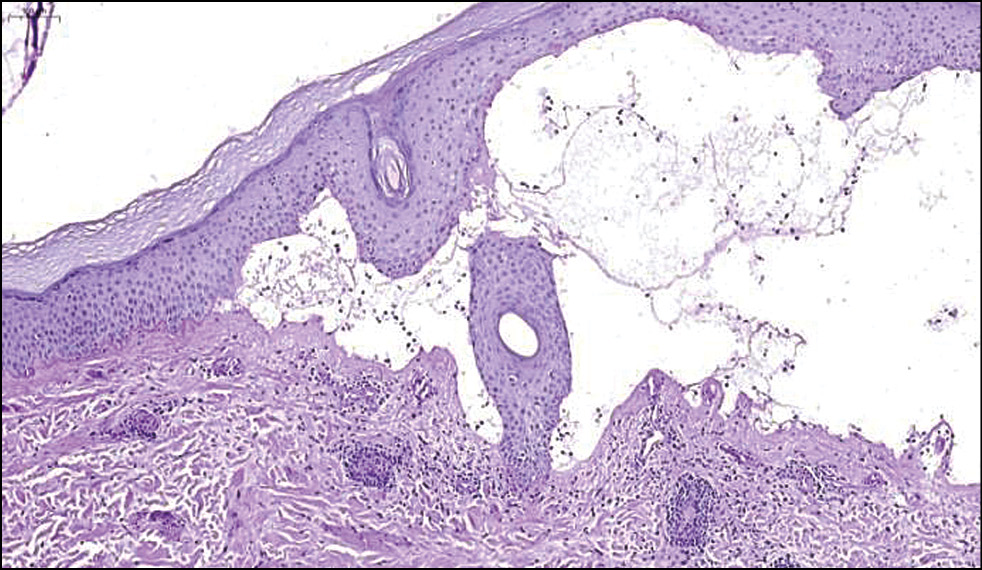

Результаты физикального, лабораторного и инструментального исследования. При постановке реакции иммунофлюоресценции определяется линейное отложение IgG, IgM вдоль базальной мембраны. В реакциях с антителами IgA свечения нет (рис. 2). При гистохимическом исследовании обнаружены субэпидермальные пузыри, состоящие из малодифференцированных фибробластов; в верхней части дермы и утолщённых стенках капилляров имеются отложения гиалина (рис. 3). В стенках сосудов выявлены ШИК*-положительные диастазорезистентные вещества (рис. 4).

Рис. 3. Результаты гистохимического исследования кожи: отложения гиалина в верхней части дермы и утолщённых стенках капилляров. ×50. / Fig. 3. Results of histochemical assay of the skin: hyaline deposits in the upper part of the dermis and thickened capillary walls. ×50.

Другим инструментом служит биопсия кожи, которая обычно не требуется для диагностики данного заболевания, но помогает при дифференциальной диагностике. При этом в литературных источниках сообщается, что результатом данного исследования при кожных порфириях, как правило, является гистологическая картина субэпидермальных пузырей и отложений иммунных комплексов [9], что соответствует гистологической картине результатов биопсии пациента в представленном клиническом случае.